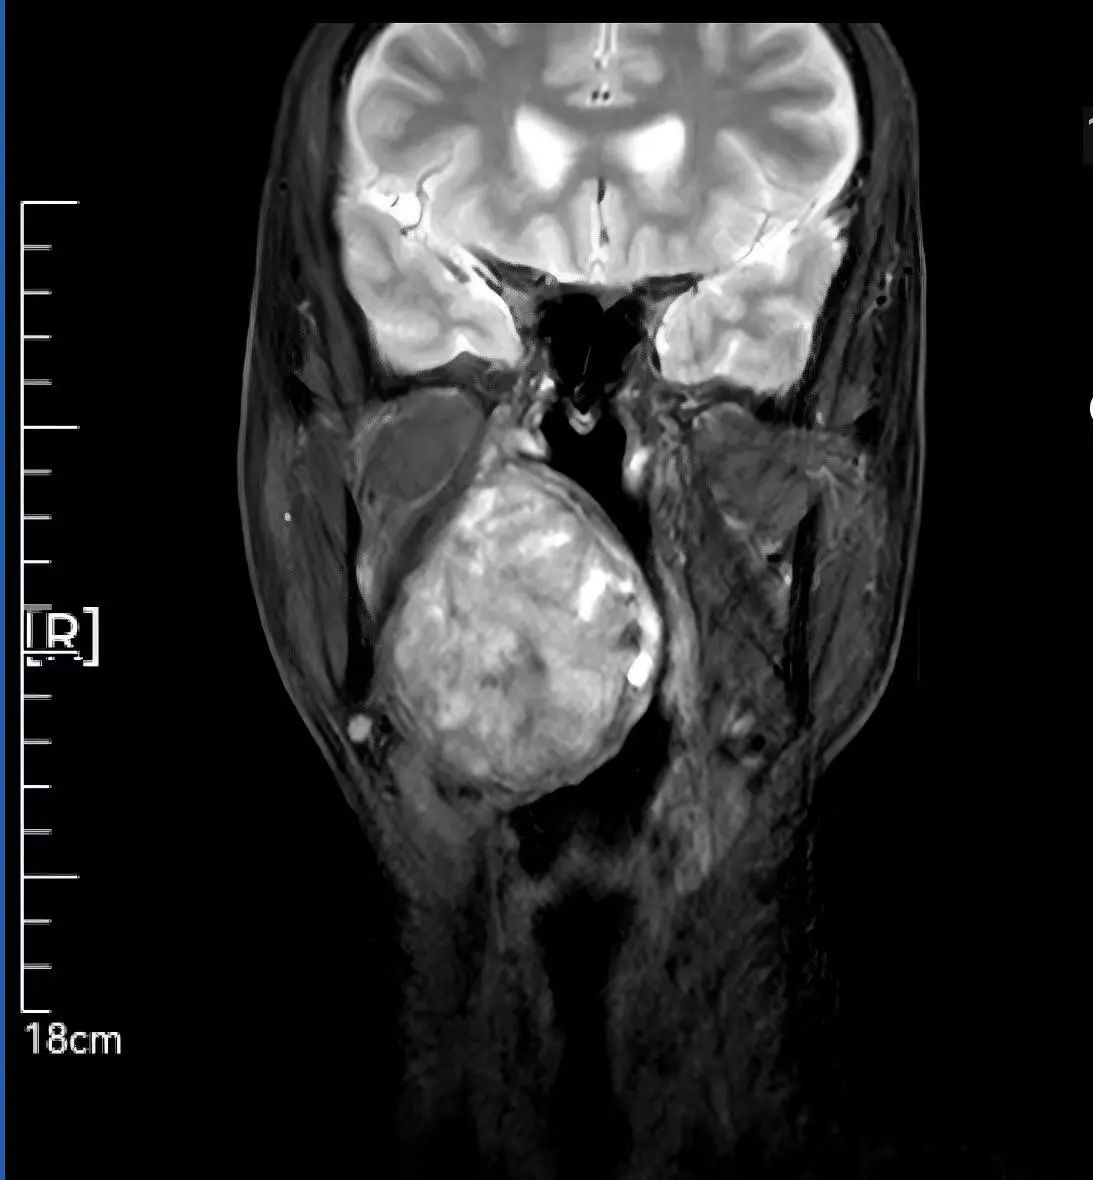

59歲患者因腭部膨隆伴吞咽呼吸困難輾轉(zhuǎn)求醫(yī),最終就診于我院頭頸外科。李智林副主任查體發(fā)現(xiàn),患者咽部明顯膨隆,懸雍垂左偏,雙側(cè)扁桃體完全被腫瘤遮蔽,口咽腔嚴(yán)重狹窄移位。影像檢查顯示,6.2×1.4×7.3cm的腫瘤深居右側(cè)咽旁間隙,穿刺病理提示,明確為涎腺來源多形性腺瘤,毗鄰頸動(dòng)脈、顱底神經(jīng)群,手術(shù)風(fēng)險(xiǎn)極高。

顯微操作實(shí)施“咽喉拆彈” 三階段方案守護(hù)神經(jīng)功能 面對(duì)“手術(shù)禁區(qū)挑戰(zhàn)”,團(tuán)隊(duì)制定精細(xì)化方案: 術(shù)前攻堅(jiān):利用MRI精準(zhǔn)定位腫瘤邊界,制定血管神經(jīng)保護(hù)預(yù)案; 術(shù)中突破:先行氣管切開建立生命通道,經(jīng)下頜骨劈開入路顯微分離腫瘤,完整保留頸內(nèi)動(dòng)脈、面神經(jīng)等重要結(jié)構(gòu); 功能重建:以鈦板固定下頜骨,最大程度恢復(fù)咀嚼功能與面部形態(tài)。 歷經(jīng)數(shù)小時(shí)顯微操作,最終實(shí)現(xiàn)了腫瘤的根治性完整切除,并奇跡般地完整保住了患者的局部核心結(jié)構(gòu)和重要神經(jīng)功能。 可視化溝通破疑慮 從“被動(dòng)治療”到“主動(dòng)共信” 面對(duì)下頜骨劈開的手術(shù)方案,患者對(duì)創(chuàng)傷及并發(fā)癥充滿擔(dān)憂。李智林副主任創(chuàng)新采用“模型+預(yù)案”可視化溝通模式,直觀演示手術(shù)路徑,并針對(duì)患者對(duì)切口美觀的需求優(yōu)化入路設(shè)計(jì)。通過“治療方案共決策”機(jī)制,患者全程參與診療討論,最終從“被動(dòng)接受”轉(zhuǎn)為“主動(dòng)信任”。術(shù)后,在護(hù)士長范改萍及病區(qū)護(hù)士長李霞護(hù)理團(tuán)隊(duì)的精細(xì)照料下,患者恢復(fù)良好,吞咽和呼吸功能逐漸改善,目前已順利康復(fù)出院。 “是你們給了我第二次生命,頭頸外科團(tuán)隊(duì)用技術(shù)解除我的病痛,用真誠治愈恐懼,這就是醫(yī)護(hù)最好的模樣?!边@段樸實(shí)的感言,成為“技術(shù)救治+人文關(guān)懷”的最佳注釋。 學(xué)科引領(lǐng)賦能精準(zhǔn)醫(yī)療 技術(shù)與溫度并重的診療范式 此次手術(shù)由頭頸外科主任李德志教授全程指導(dǎo),依托科室多學(xué)科協(xié)作(MDT)體系與顯微外科技術(shù)優(yōu)勢(shì),實(shí)現(xiàn)“精準(zhǔn)切除-功能保留-人文關(guān)懷”三重突破。未來,團(tuán)隊(duì)將以更前沿的醫(yī)療技術(shù)、更溫暖的人文關(guān)懷,不斷攀登醫(yī)學(xué)高峰,守護(hù)區(qū)域內(nèi)百姓頭頸健康,為生命安全構(gòu)筑堅(jiān)實(shí)防線。